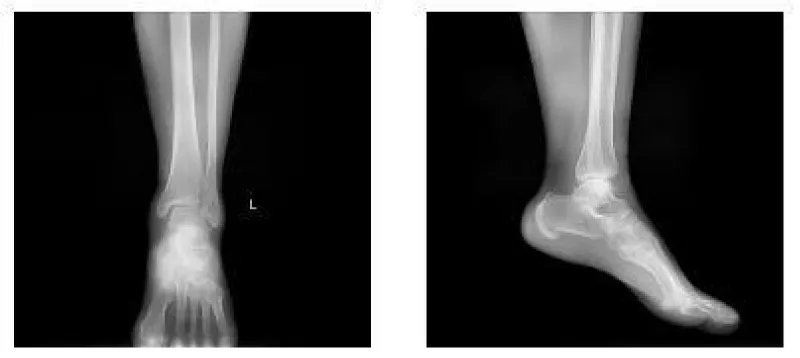

A 56-year-old woman was sent to the emergency department by her family. She sprained her left ankle when she went down the stairs. She had difficulty walking because of a painful left ankle. Specialized physical examination found tenderness in the anterolateral distal tibia and fibular neck. X-ray showed fractures in the tibia lateral border and fibular neck, with no evidence of inferior tibiofibular joint dislocation (Figures 1,2). A computed tomography scan confirmed the presence of Tillaux-Chaput and Volkmann fractures (Figures 3-5).

The anesthetic for the operation was lumbar anesthesia. A posterolateral approach was used to expose the Volkmann fracture. An anterior tibial approach was used to expose the Tillaux-Chaput fracture. The inferior tibiofibular joint was checked carefully. Fractures were reduced and then fixed. Volkmann fracture was fixed by buttress plate, and Tillaux-Chaput fracture was performed by hollow screw. Hook test intraoperative was negative. Anatomical reduction and perfect stability were confirmed by X and CT postoperatively (Figures 6.7). CT scan in the transverse section confirmed that the anterior and posterior edge of the distal fibula is in an arc with the fractures of the tibia. It meant there was no dislocation of the distal fibula. The anterior and posterior ligaments of the inferior tibiofibular ligament are in good condition.